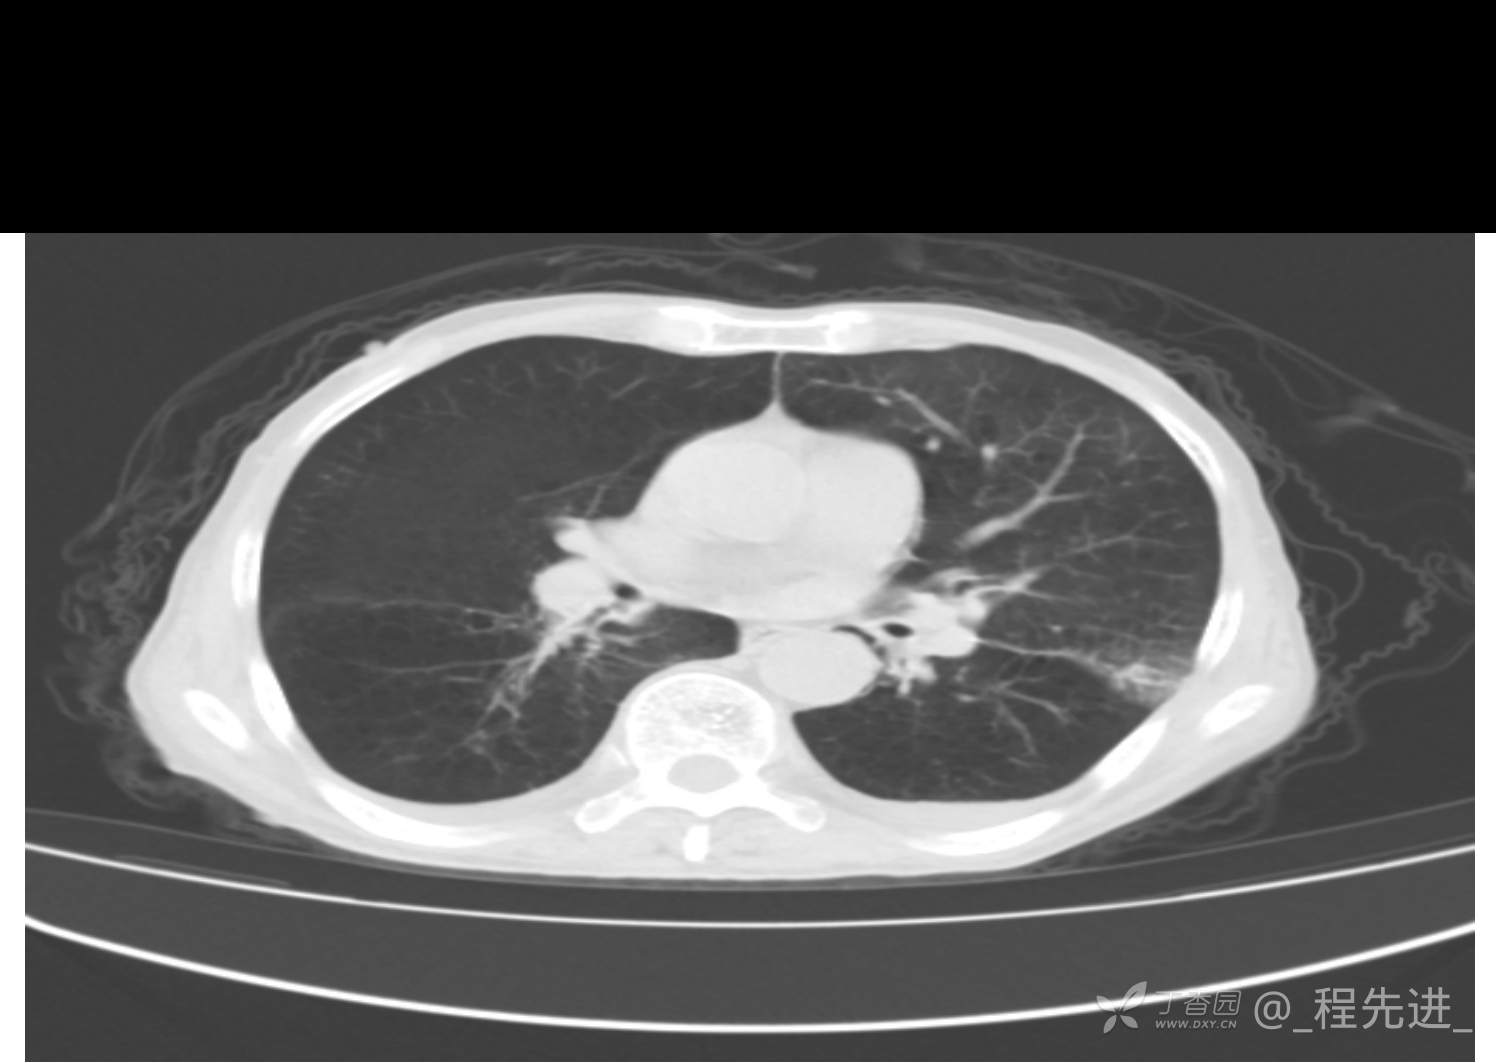

患者性别:男

患者年龄:81岁

简要病史:反复咳嗽、咳痰20余年,加重1周。两肺呼吸音低,可闻及散在干湿啰音。